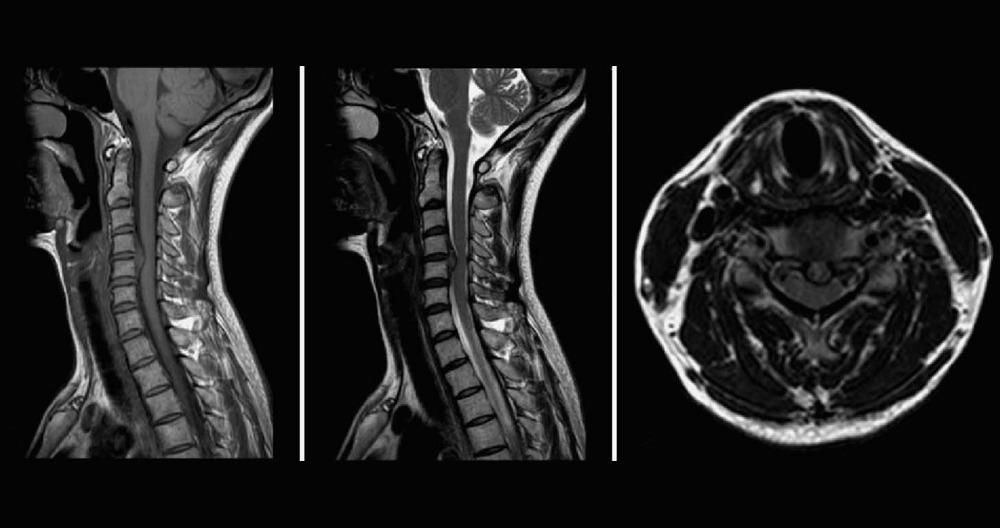

Herniated Cervical Disc MRI

Stress testing of the cervical spine reveals increased pressure to the spine when it is in an upright position. It also includes flexion and extension views (looking upward and downward). When a patient lies down during traditional supine MRI, the stress on the discs is minimal. It may show a slight disc bulge or nothing at all. The disc material is compressed when the table is tilted vertically. This causes the disc material to protrude or herniate, pinching the spinal cord, and causing pain.

In flexion, you look downwards to increase pressure on the disc. This can cause spinal cord compression and herniation growth. Many patients report feeling more pain or numbness at the fingertips. Supine images often fail to show disc herniation and spinal cord compression. MRIs taken in weight bearing or flexion/extension reveal the source of the patient’s pain.

The Stress Test MRI is used to help doctors understand and diagnose positional symptoms. Although patients may feel relief when they lie down, pain, numbness and weakness often increase when the patient is in an upright or weight-bearing posture.

Diagnostic, weight bearing images can show pinched nerves and injured discs. These images may be able to explain the patient’s symptoms in a way that is not possible with traditional supine imaging. Traditional supine MRIs may miss up to 30% of spinal injuries. Ask for a Stress Test MRI if you feel more pain or numbness while standing or sitting. This is your MRI – do not lie down.

Magnetic Resonance Imaging (MRI), a noninvasive scan that uses a magnetic field in combination with radiofrequency waves, gives a detailed view to the soft tissues of the spine. Contrary to X-rays, nerves and discs can be clearly seen. The dye (contrast agent), may be injected into your bloodstream. An MRI will detect the disc that is damaged and any nerve compression. An MRI can detect bone overgrowth, spinal cord tumors or abscesses.

Advanced diagnostics are available if more information is required to confirm the diagnosis. This would most commonly include an MRI scan. It uses a strong magnet that images the cervical spine to show whether a disc has moved onto a nerve root. A CT scan with myelogram, which is dye injected into the spine to view soft tissues, could be used to image the cervical spine if a patient is unable or unwilling to undergo an MRI.